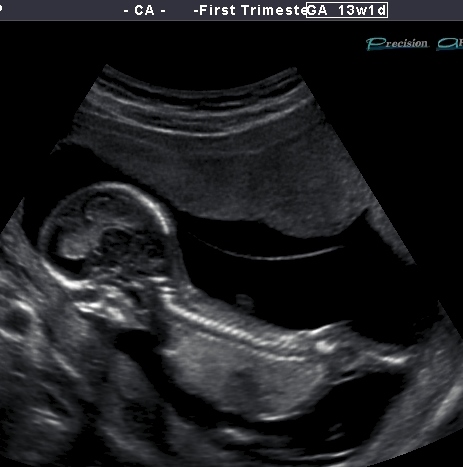

Elico's 13 week 1 day u/s pic

Hi there. I had my NT scan today and wow that bubba was hypo. The sonographer was struggling to get the correct info that was required of her. I was watching the scan closely and i saw nubs every so often and it was on an angle upward but not extremely vertical .... The pics i have of bub are just a handful of cute pics my lovely scanner put on a disk because hubby couldn't attend. i will get the whole lot of pics on monday where hopefully there will be more nub pics. So this is my only pic and im not even sure its a nub unless its a see through the leg one lol. Any advice appreciated.Attachment 12418